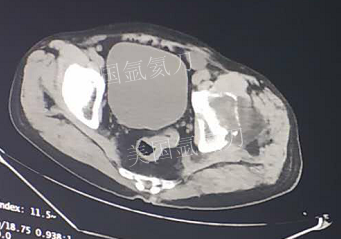

73岁臀部氩氦刀冷冻消融

发布人:美国氩氦刀技术官方网站    发布时间:2019/2/21 13:51:52